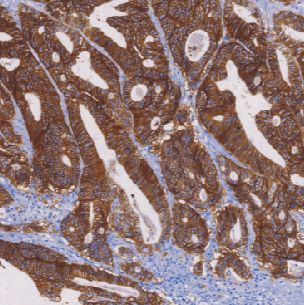

上皮抗原在上皮细胞中广泛分布,在上皮来源的肿瘤中具有高度保守性表达的特性。腺癌细胞阳性反应表现为弥散的胞质、胞膜着色;而间皮瘤则是少量细胞弱的局灶性胞质着色或阴性表达。

- 阳性部位:胞膜

- 适用组织:石蜡切片

- 预处理:热修复